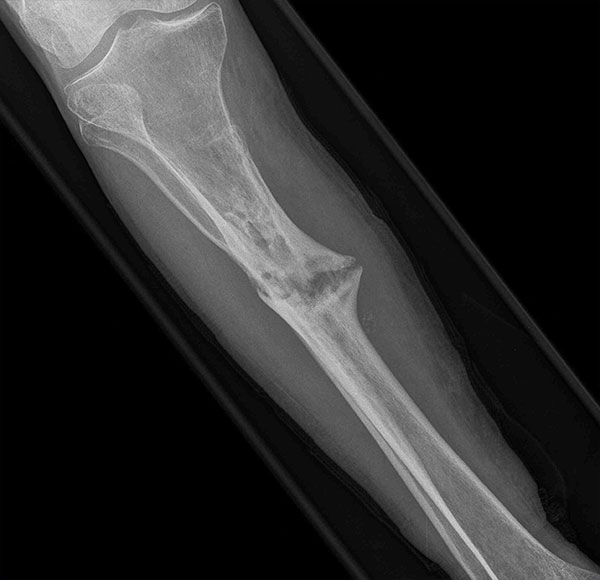

- Focus Area Reconstructive Surgery & Non-Surgical Management to Improve Bone Healing

- Sponsor DoD OETRP

- Primary Objective RCT to evaluate the use of recombinant protein in patients at high risk for nonunion